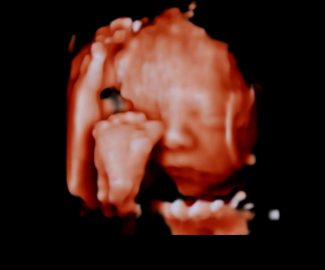

Especialista en diagnóstico por imágenes con más de 25 años de experiencia en el campo del ultrasonido y radiología digital. Trabajamos con equipos de alta tecnología garantizando la calidad y seguridad de nuestros diagnósticos, pues nuestra prioridad es la salud, bienestar y satisfacción de nuestros pacientes.

Sabemos que visitar un centro médico a veces genera nervios. Por eso, hemos creado un ambiente cálido, moderno y 100% seguro para ti. Desde nuestra cómoda sala de espera hasta nuestras áreas de ecografía, mamografía y rayos X, cada rincón está equipado con tecnología de última generación y diseñado para que te sientas en confianza.